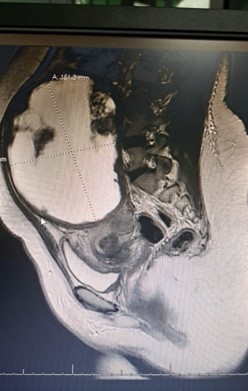

MRI of the pelvis with contrast reported bilateral ovarian dermoid cysts, with the largest measuring approximately 67×64 mm, containing fat and calcification components consistent with mature cystic teratoma. The uterus was described as unremarkable.

Figure 1: Sagittal pelvic MRI showing a large mass arising from the uterine fundus.

Large leiomyomas can present diagnostic challenges when imaging findings overlap with adnexal masses. MRI is generally the preferred modality for characterization of uterine tumors; however, extremely large leiomyomas may distort anatomy, leading to misinterpretation. In this case, the mass effect displaced the uterus posteriorly while mimicking bilateral ovarian dermoid cysts due to heterogeneous signal intensity.

Figure 3: MRI sagittal section showing a large heterogeneous pelvic–abdominal mass initially interpreted as an ovarian lesion.